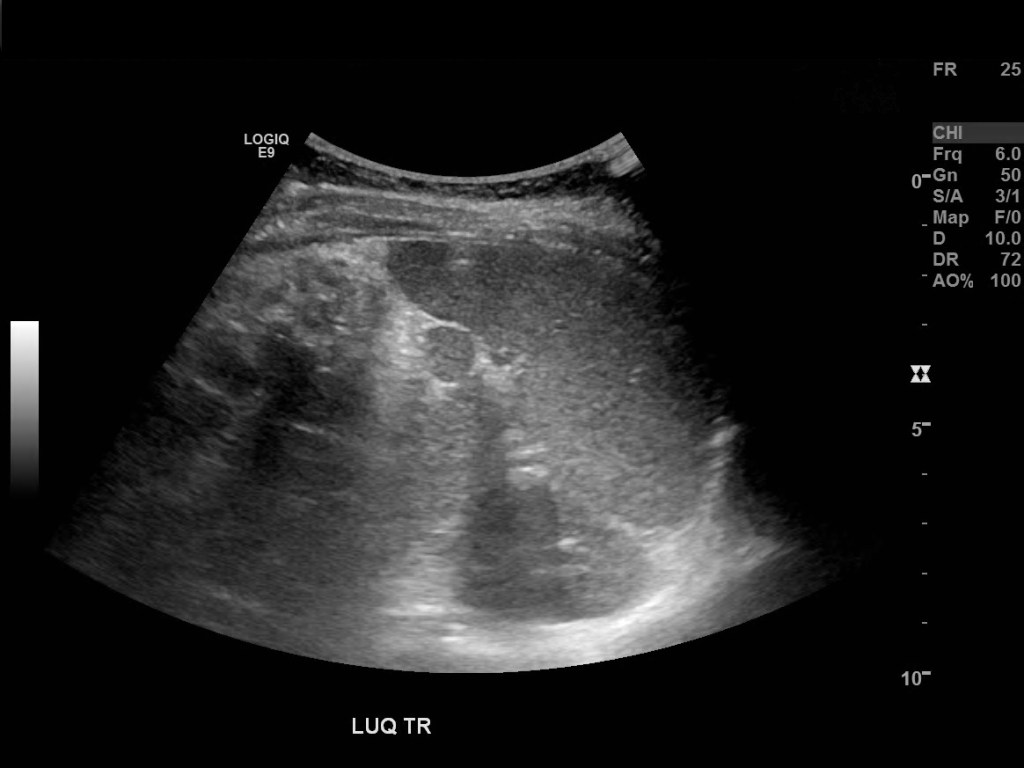

An accessory spleen is normal splenic tissue separate from the main mass of the spleen. Accessory spleens vary in size from a few millimeters to several centimeters, they occur most frequently near or at the splenic hilum. They are also quite common found in up to 16% of CTs of the abdomen and up to 30% of autopsies [1]. For the uninitiated the splenule may be mistaken for a tumorso it is important that the sonographer is aware of this variant. Splenunculi also occur post splenectomy, and may enlarge, although they usually retain a spherical shape. [2]

The most common location to find a splenule is by the splenic hilum however they have been documented in other parts of the body as close as the stomach and pancreas and as far as the scrotum. [3,4]